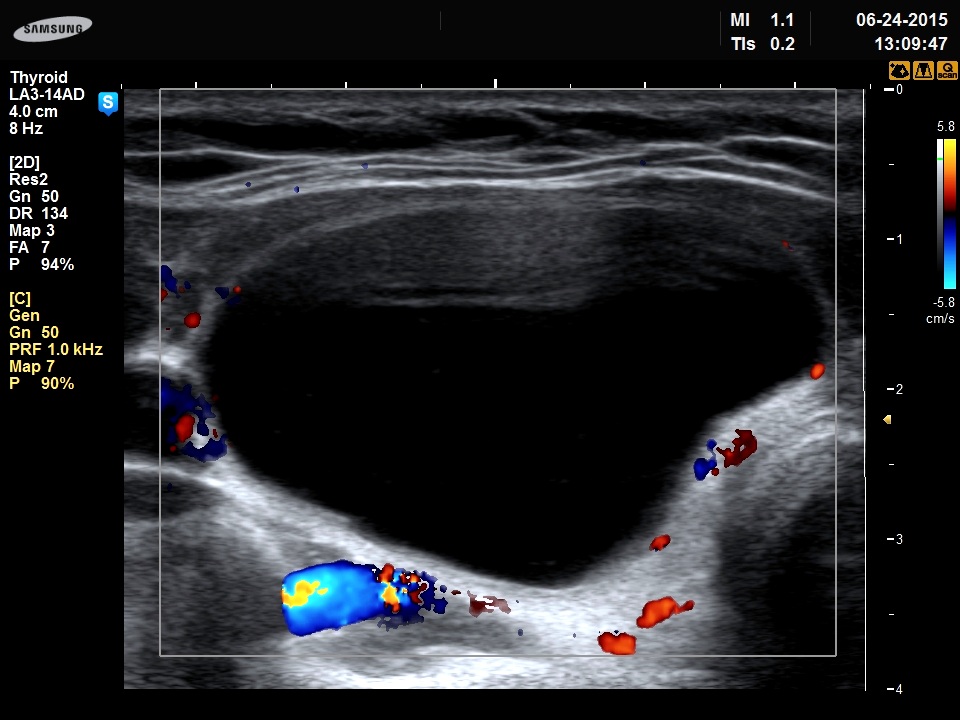

Right lobe, transverse scan, color Doppler mode. The lesion presents signs of perinodular blood flow.